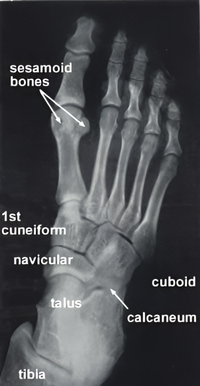

The word [sesamoid] means "similar to a sesame". First used by Galen c.180AD, he describes small ovoid bones that are "similar to a sesame seed", referencing the seed of the plant sesamum indicum, the oil of which was used as a laxative at that time.

Sesamoid bones are found in the tendons of some muscles and are mostly inconstant. Largey and Bonnet proposed a classification for these bones as: accessory, capsuloligamentous, intratendineous, and mixed.

Of special interest to this article are the sesamoid bones found within the two tendons of the flexor hallucis brevis muscle in the base of the foot (see accompanying X-ray image). These bones, especially the medial sesamoid bone, was attributed religious, mystical, and magical powers since ancient times. This is due to the fact that this small bone is highly resistant to natural decomposition. A Hebrew medical text dated 210 BC, attributed to Ushaia presented a small bone he called "luz" as the "depository of the soul". Many other authors, including Vesalius (who called it Albadaran), believed that upon resurrection, the whole body could reform from this "seed" bone.

This belief was later reinforced by religious texts into the early Renaissance which stated that this bone was indestructible and its presence was enough to guarantee resurrection for believers.

Note: The original X-ray was published here courtesy of Wesley Norman, PhD in his website. The website is no longer available, so the image is now in the public domain via www.archive.org.